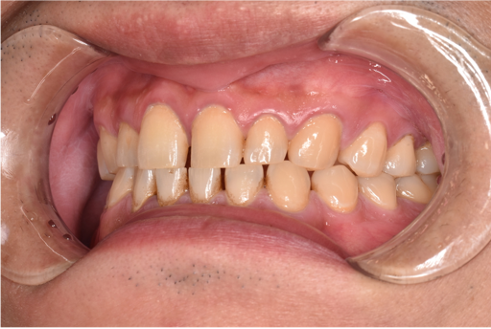

治療前

| カウンセリング・診断結果 | こちらの患者様は1日20本ほどタバコを吸われる方で、歯医者は十数年振りとのことでした。 縁上歯石と全体的に縁下歯石が付着しており、歯ぐきが赤く腫れ炎症しておりました。前歯の歯頸部や裏側に着色も認められました。歯周病検査により中等度の歯周炎が認められたため歯周治療も必要でした。 |

| 行ったご提案・治療内容 | 初診時はブラッシング方法などセルフケアについて説明を行い、縁上歯石・着色の除去を行いましました。 歯肉の炎症がある程度落ち着いたところで、後日再評価を行い歯周治療へ移行しました。 |